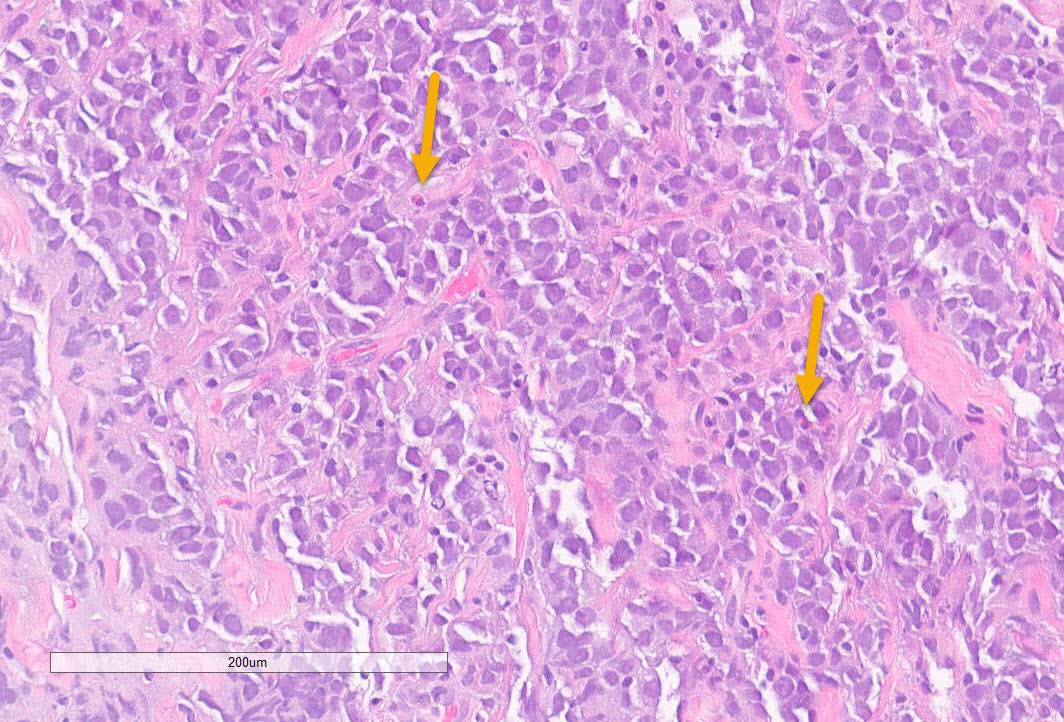

Jerad Gardner, MD on Twitter "RT atman_ci Pathology PathTwitter Zoster Differentials Varicella zoster (commonly known as chickenpox) and herpes zoster (commonly known as shingles) are caused by the same herpes virus. Herpes zoster, also known as shingles, results from activation of latent vzv from a sensory ganglion. Herpes zoster (also known as shingles) typically presents with pain described as burning or stabbing, followed by a vesicular. Varicella follows the initial infection. Zoster Differentials.